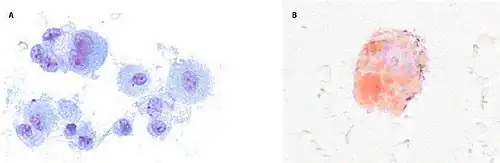

Bronchoalveolar lavage specimens may exhibit an increased level of neutrophils in combination with lymphocytes and vacuole-laden macrophages.[22] Lavage cytology with oil red O staining demonstrated extensive lipid-laden alveolar macrophages.[66][67] In the few cases in which lung biopsies were performed, the results were consistent with acute lung injury and included a broad range of features, such as acute fibrinous pneumonitis, diffuse alveolar damage, lipid-laden macrophages, and organizing pneumonia.[41][62] Lung biopsies often showed neutrophil predominance as well, with rare eosinophils.[64]